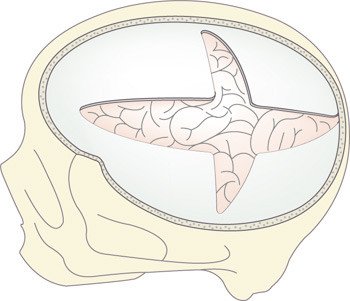

Pasienten (i narkose) legges på ryggen med hodet dreid fra infarktet. Hudsnittet legges langs midtlinjen fra pannen mot occiput og videre lateralt like over forløpet av sinus transversus, så over og foran øret mot arcus zygomaticus. Kraniotomien gjøres i ett stykke «fra sinus til sinus til sinus»: Fra arcus, over tinningbeinet forbi sutura lambdoidea og fremover langs midtlinjen, uten å åpne pannebihulen. Sporet går videre parallelt med gulvet i fremre skallegrop. Lille kilebeinsvinge drilles ned epiduralt, som illustrert i figur 2. Selve hemikraniektomien gir noe trykkreduksjon, men for å oppnå best avlastende effekt bør dura åpnes (37). Dura åpnes i et kors eller ved et stjerneformet snitt ut til beinkantene, deretter kan et implantat skyves innunder og om nødvendig festes med enkle suturer. Hjernen vil oftest protrudere gjennom åpningen, og en stor hemikraniektomi med diameter over 12 cm anbefales (35, 36) for å redusere skjærekrefter og venøs stase, som kan øke ødemet. Blødning epiduralt eller i musculus temporalis kan kreve reoperasjon (36).